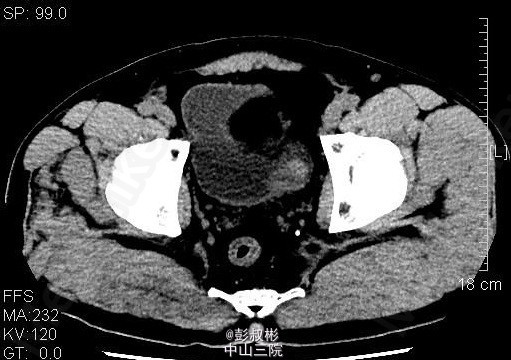

男性,54岁,血尿1月余。盆腔CT:膀胱左侧壁肿块,约27×23mm,考虑膀胱癌可能性大。患者家属要求保留膀胱,中腹部CT平扫+增强扫描+CTU,结合CTU:膀胱左侧可见一充盈缺损影,大小约34×25mm,双侧肾盂肾盏未见扩张,其内未见异常密度影,双侧输尿管通畅,未见增宽或狭窄。双肾大小、形态未见异常,双肾可见多发低密度影,CT值-15~15HU,最大约14×13mm,增强扫描强化不明显。双侧肾上腺大小、形态未见异常,其内未见异常密度影,增强扫描未见异常强化。膀胱充盈良好,膀胱左后壁可见一类圆形肿块向腔内突出,大小约34×25mm,增强扫描可见明显强化。前列腺不大,其内未见异常密度影。胆囊体积不大,囊壁增厚,可强化,其内未见异常密度影。片内所见肝实质密度普遍性减低,CT值约48HU,低于同层面脾实质CT值。